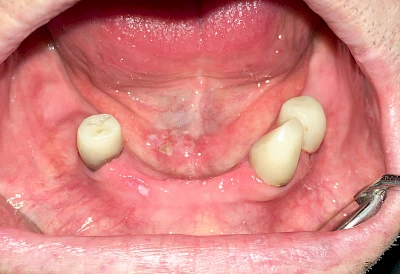

Mandelstein

Mandelsteine (Tonsillenstein oder auch Tonsillolith) sind Reste von Gewebe, Speisen, Entzündungszellen und Bakterien können vereinzelt im Bereich der Gaumenmandeln beobachtet werden. Ggf. sollten die aktuellen Mundpflegemaßnahmen überprüft und ggf. angepasst werden.